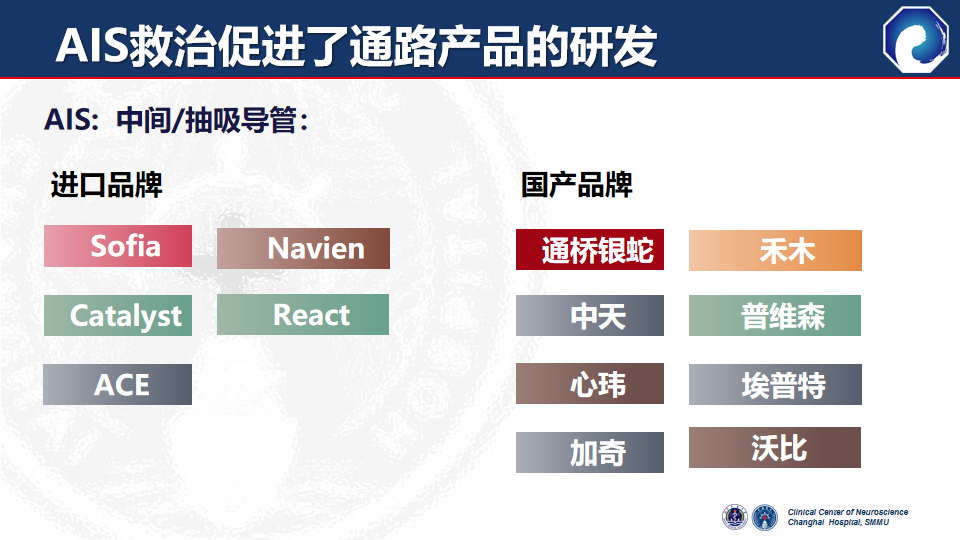

AIS救治促进了通路导管的研发